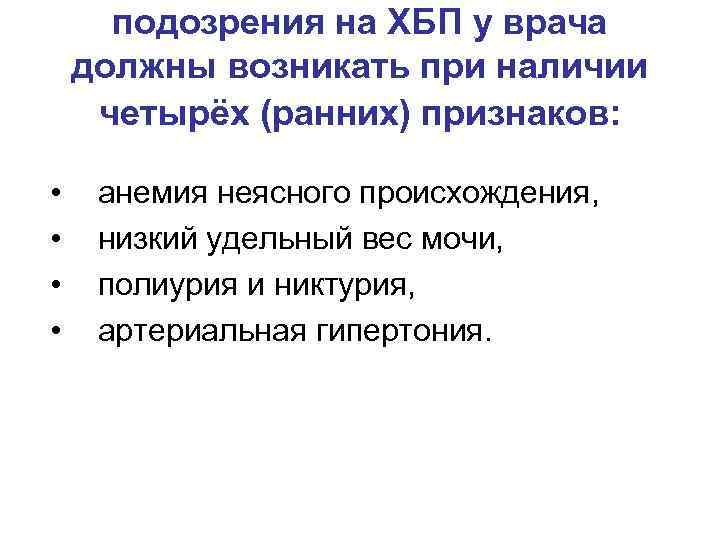

подозрения на ХБП у врача должны возникать при наличии четырёх (ранних) признаков: • • анемия неясного происхождения, низкий удельный вес мочи, полиурия и никтурия, артериальная гипертония.

подозрения на ХБП у врача должны возникать при наличии четырёх (ранних) признаков: • • анемия неясного происхождения, низкий удельный вес мочи, полиурия и никтурия, артериальная гипертония.